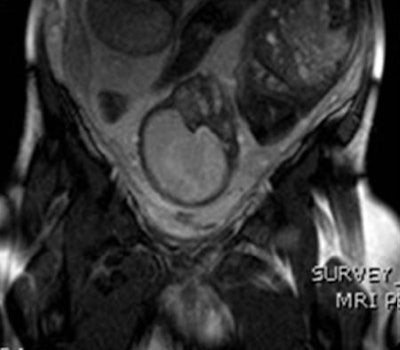

Better bladder filling after maternal hydration allows for further identification of areas of focal invasion of the uterine wall and possibly the bladder wall (arrows) from the anterior placenta, which was characterized increta and possibly percreta. On surgery, invasion of the bladder wall was not confirmed.Abnormal placenta was revealed in 21 cases: four cases of acreta, 11 cases of increta, and six cases of percreta. In one case, the presence of fibromas complicated sonographic appearances and was clarified by MRI.